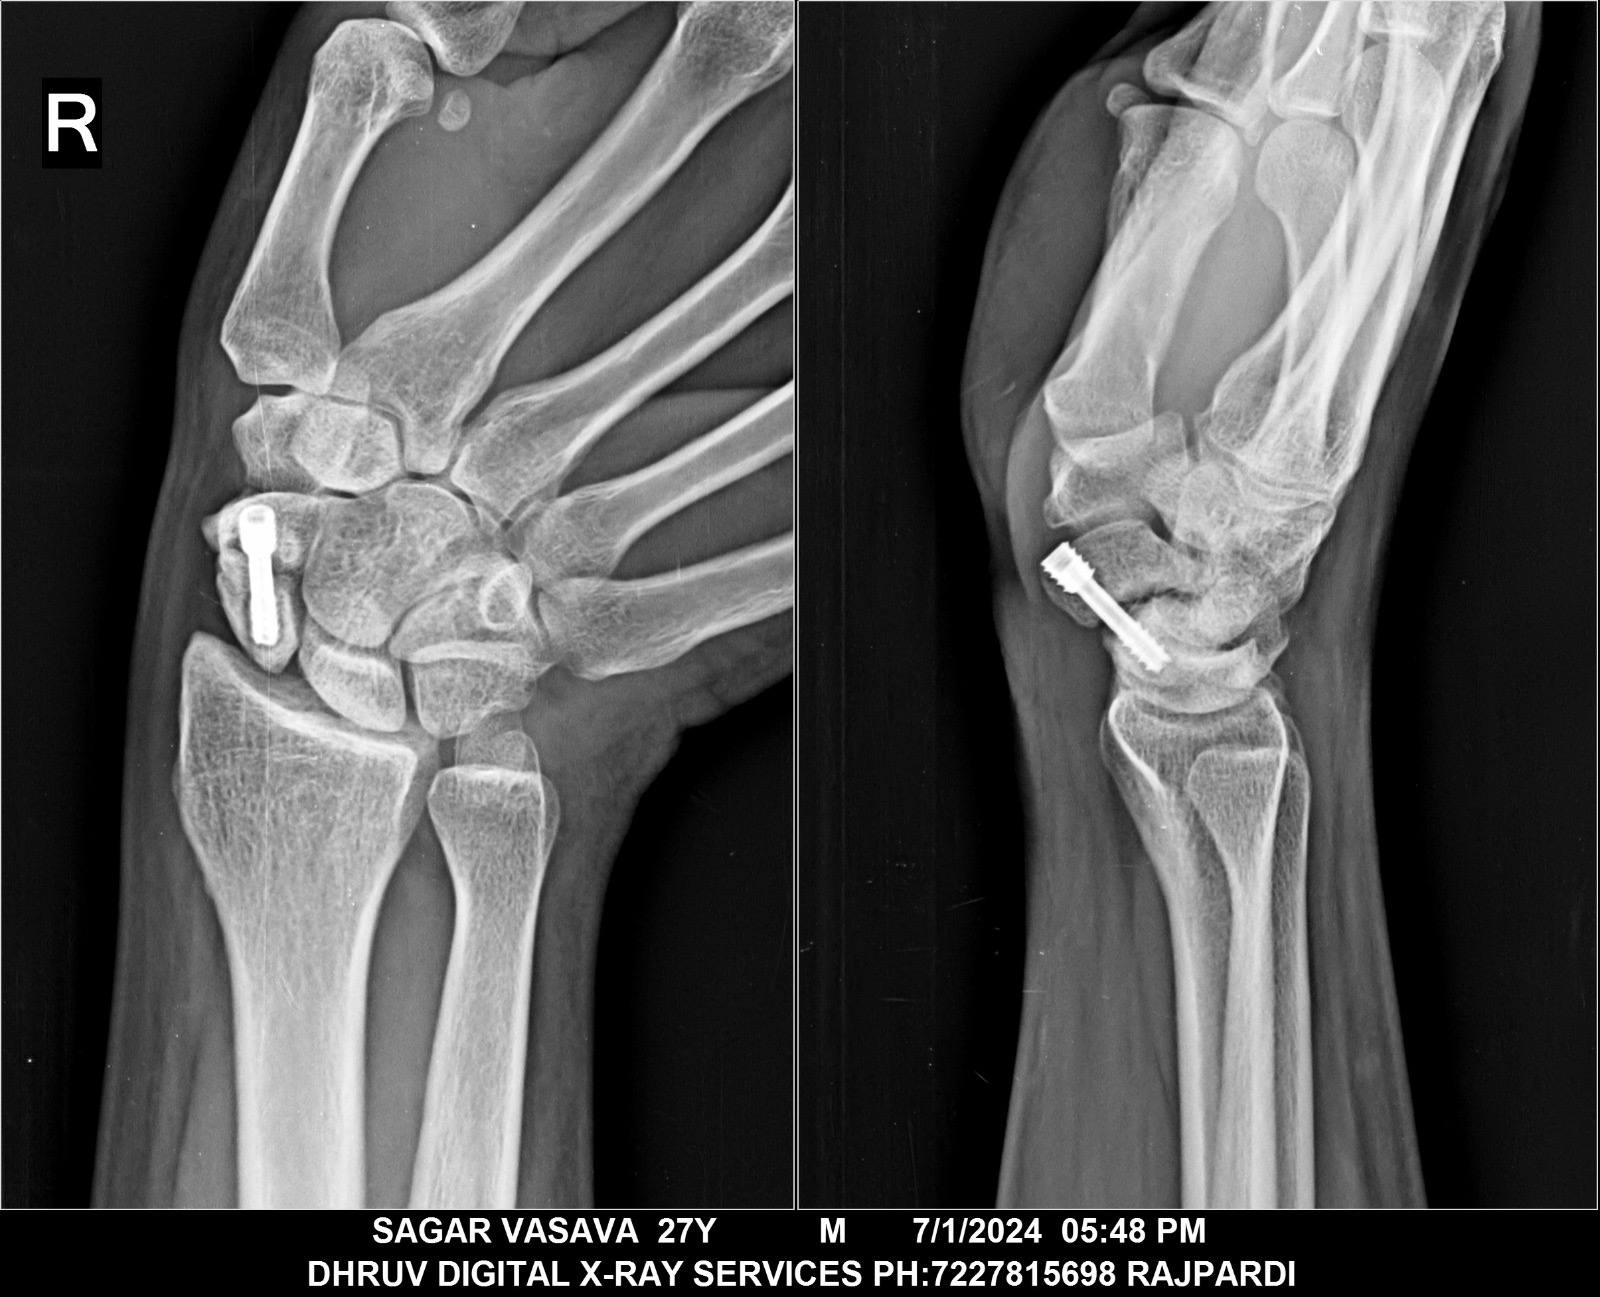

Hi sir me sagar vasava gujarat se hu

Sir 2019 me scaphoild non union ki surgery ki thi.lekin abhi bhi fracture he kya kru kuch samaj nai aa rha.yaha pe doctor ko dikhaya to bole 4 corner fusion or SNAC krne to bole. Sir kuch suggestion dijiye.